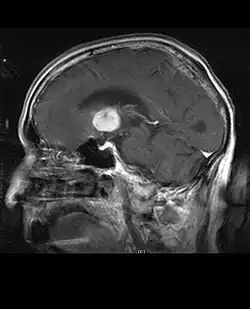

A tomografia computadorizada (TC) e a ressonância magnética (RM) podem detectar efetivamente uma neoplasia no cérebro. A RM é mais sensível que a TC para identificar lesões, mas contraindicações para pacientes com marcapasso cardíaco, próteses incompatíveis, clipes metálicos e outros. A TC continua sendo o método de escolha para detectar calcificações dentro de lesões ou erosões ósseas da calota craniana ou da base. A utilização de agentes de contraste, que são iodados no caso da TC e paramagnéticos ( gadolínio ) no caso da RM, permite a aquisição de informações sobre a vascularização e integridade da barreira hematoencefálica, uma melhor definição do tumor tumoral comparado ao edema circundante e à geração de hipóteses sobre o grau de malignidade . O exame radiológico também permite avaliar os efeitos mecânicos e consequentes alterações nas estruturas cerebrais decorrentes do tumor, como hidrocefalia e hérnias, cujos efeitos podem ser fatais. Finalmente, na preparação para a cirurgia, esse diagnóstico pode ser usado para determinar a localização da lesão ou a infiltração do tumor em áreas vitais do cérebro. Para isso, a RM é mais eficiente que a TC, pois pode fornecer imagens tridimensionais.

As ferramentas de diagnóstico por imagem radiológica destacam a mudança no tecido neoplásico em comparação com o parênquima cerebral normal (através de alterações na densidade do tecido fotografado eletronicamente na TC e na intensidade do sinal na RM). Como a maioria dos tecidos patológicos, os tumores também são reconhecidos por um acúmulo aumentado de água intracelular. Na tomografia computadorizada aparecem hipodensa, ou seja, de menor densidade que o parênquima cerebral, na tomografia de ressonância magnética nuclear com relaxamento spin-lattice T 1 hipointenso e em relaxamento spin-spin T 2 bem como a ponderação de prótons (PD) hiperintensa.

No tecido tumoral, em geral, a maior proporção de realce pelo contraste se deve à barreira hemato-tumor particular que permite a passagem de iodo (TC) e gadolínio (RM) para o espaço intersticial extravascular intratumoral. Isso aumenta o sinal (densidade ou intensidade) do tumor. No entanto, deve-se ter cuidado para garantir que o realce do contraste não diferencie definitivamente a neoplasia do edema periferida. De fato, o achado anátomo-patológico no tecido tumoral de glioma infiltrante maligno, como no glioblastoma e no astrocitoma anaplásico, também mostra além do edema vasogênico causado pela destruição da barreira hematoencefálica pelo tumor. Esta última condição clínica é pouco detectável pelo diagnóstico por imagem.

Na ressonância magnética, um tumor intracraniano aparece como uma lesão maciça que pode se tornar mais luminescente após o uso do agente de contraste. No entanto, há sempre uma anomalia de sinal na ressonância magnética, que indica a presença de neoplasia ou edema vasogênico. Normalmente, o aumento da luminescência (realce pelo contraste) é indicativo de um tumor de grau mais alto de malignidade. Um anel contrastante é característico do glioblastoma, com a porção luminescente correspondendo à parte vital do tumor maligno e a área mais escura-hipointense à necrose tecidual.